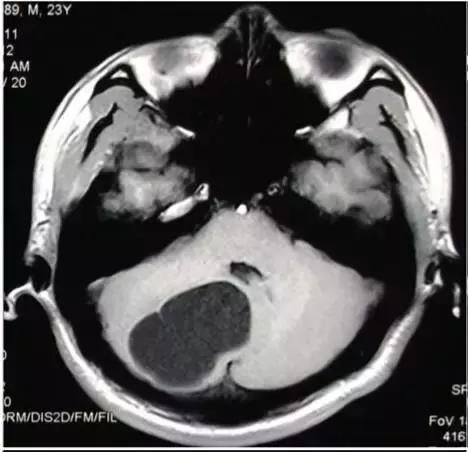

皮样囊肿破裂